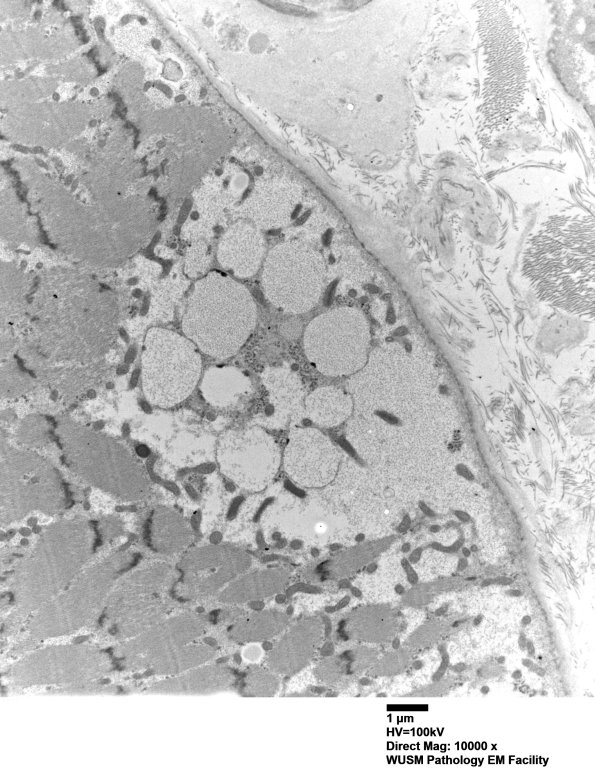

Washington University Experience | METABOLIC | Pompe Disease | 5D13 Muscle (Case 5) EM025 - Copy

5D13 Muscle (Case 5) EM025 - Copy

5D13,14 There are multiple membrane bound elements under the sarcolemma. (electron micrographs)